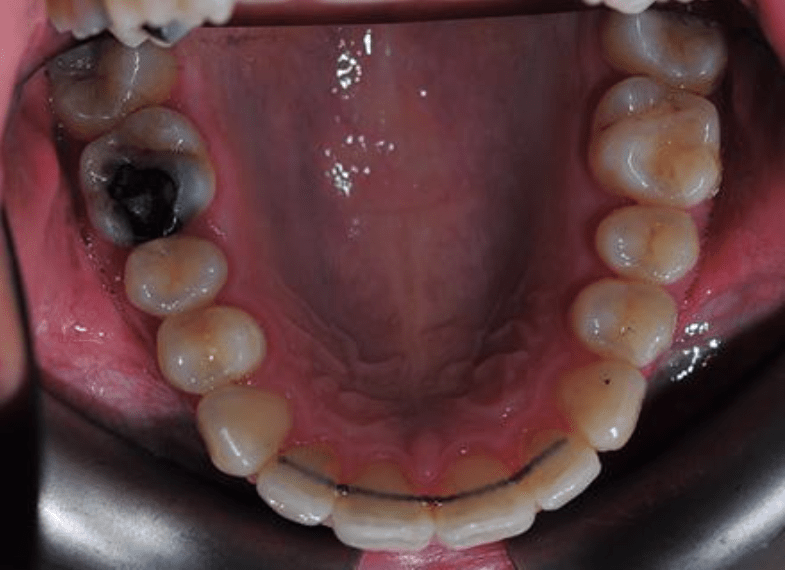

This case took under 12 months to straighten the very crooked teeth in the lower jaw and align the uppers as well. The finished photos show a fixed permanent wire on the inside of the teeth to stop them relapsing or moving back. Permanent wire retainers and night-time removable retainers are always recommended.